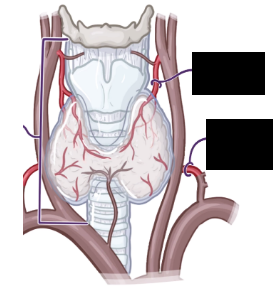

Label the thyroid arterial supply

A

Superior thyroid a:

• 1st branch of ECA

• Inserts inf poles

Inferior thyroid a:

• Branch of subclavian artery

• Inserts post aspect of inf poles

Thyroid ima a:

• 1-% of people

• Usually arises from brachiocephalic trunk

Label the thyroid venous drainage

Superior + middle thyroid veins drain –> IJV

Inferior thyroid veins drain –> brachiocephalic vein